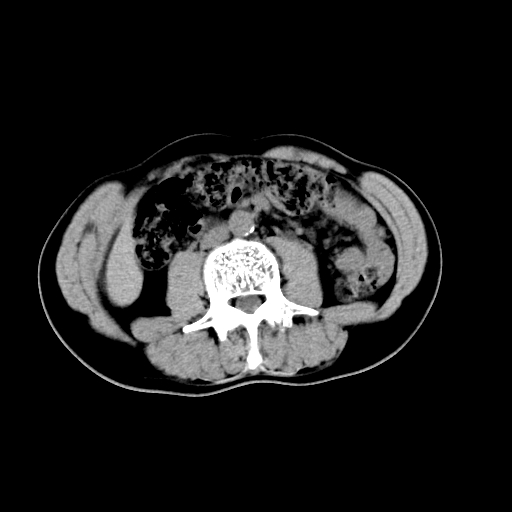

男,47岁,左输尿管结石碎石治疗后10余日。彩超示:左输尿管下段狭窄、输尿管积水。请各位讨论一下左输尿管下段结石还是静脉石?

两侧髂总动脉壁斑状及点状钙化.左侧输尿管行经与左髂总动脉相交后见高密度影,且下段输尿管管腔未见扩张,应该要考虑结石伴以上输尿管及肾盂积水.但右侧结节状高密度影,也应该是结石吧!那以上输尿管未见扩张呢!因此静脉结石可能性也较大.请问楼主碎石前左侧输尿管结石位置.

虽左侧有轻度肾盂积水但不支持结石。1结石边周应该有软组织包绕呈晕征。2钙化点前面见输尿管影也不支持是结石。3彩超没提结石。建议超生复查。

输尿管先位于腹部,后进入盆腔,最后斜穿膀胱壁开口于膀胱,因此,临床上常将输尿管分为腹段、盆段和壁内段。第1个狭窄:在肾盂与输尿管移行处。第2个狭窄:在跨过髂血管处。第3个狭窄:在穿过膀胱壁处。这些狭窄是结石容易滞留的部位。

建议:把输尿管、膀胱扫全,除外输尿管下端结石,必要时强化或泌尿系造影除外其他.

左侧输尿管有轻度扩张伴有肾盂积水,输尿管下段周围的高密度影不象在输尿管内。

同意,不支持结石。(因显示该高密度影前见扩张输尿管影,另外两侧对称显示)。

左侧高密度影在左侧输尿管的内侧方,所以不考虑输尿管结石.

我认为不是结石的可能性大,因为他的位置和血管钙化的位置邻近